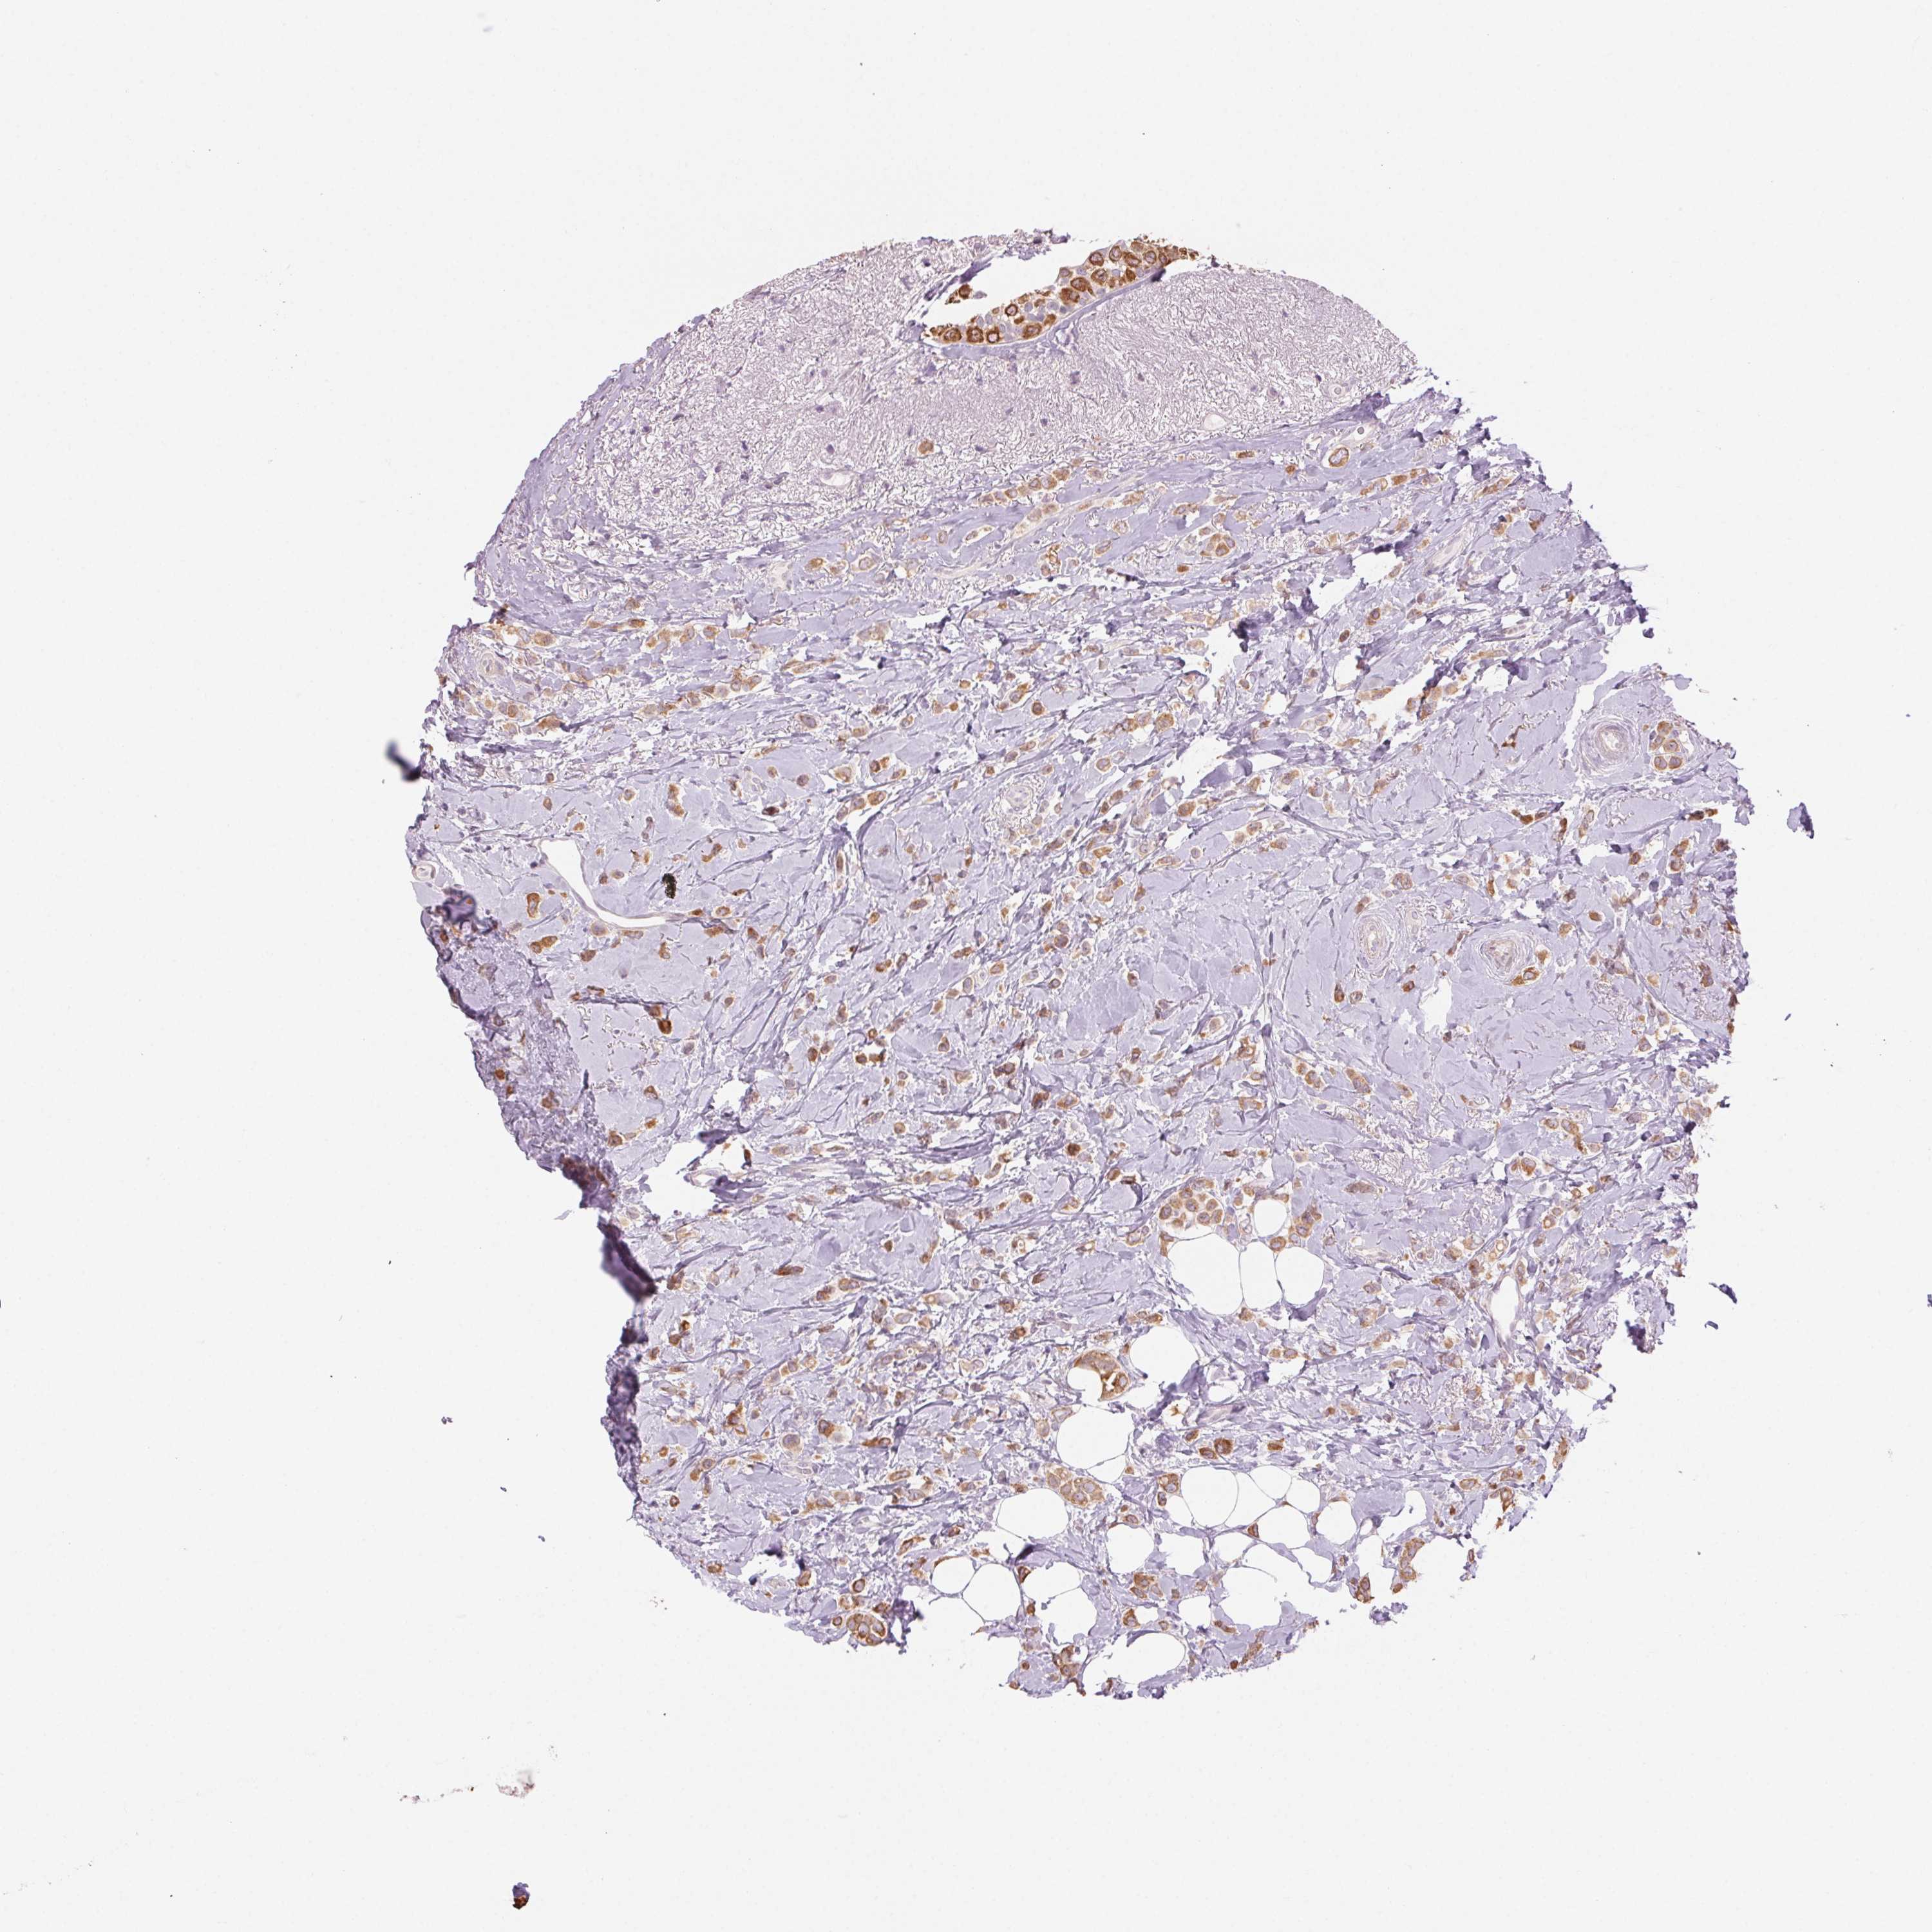

CANCER BREAST CANCER Show tissue menu

BRCA TCGA BRCA VALIDATION PROTEIN EXPRESSION

Breast cancer

Human cancer

Breast invasive carcinoma

HHLA2 is not prognostic in Breast Invasive Carcinoma (TCGA)